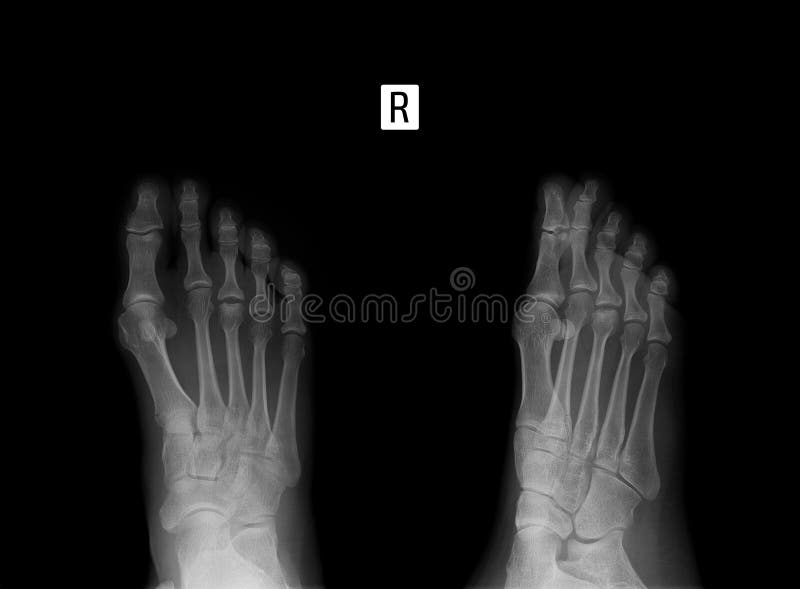

Scopriamo i tipi di frattura, cause, cure e tempi di recupero! La frattura del quinto metatarso si verifica spesso insieme a una distorsione della caviglia, specialmente quando la caviglia ha ruotato verso l'interno.

Il piede è una struttura anatomica fondamentale sulla quale agiscono tutti i carichi generati dal movimento corporeo. La frattura del quinto metatarso può essere determinata da diverse cause: Al termine dovrò fare una nuova rx del piede dx e nel caso nn ci sia sufficiente callo osseo di rimetterlo.

Il piede è una struttura anatomica fondamentale sulla quale agiscono tutti i carichi generati dal movimento corporeo. Las fracturas del quinto metatarsiano son muy comunes. Piove sul bagnato in casa rossoblù. ¿cómo se cura una fractura del quinto metatarsiano? La frattura del quinto metatarso si verifica spesso insieme a una distorsione della caviglia, specialmente quando la caviglia ha ruotato verso l'interno. E' una frattura molto frequente nella traumatologia ortopedica, e colpisce indifferentemente sia uomini che donne. Il quinto metatarso si trova all'esterno del nostro piede, è l'osso che si collega al mignolo, un'area delicata che può essere fratturata prima di un colpo, una distorsione o una distorsione maggiore, una lesione nota come frattura di jones. Parliamo della frattura del quinto metatarso, l'osso posizionato sul mignolo del piede. Fractura del quinto metatarsiano del pie. La frattura di jones provoca dolore e infiammazione all'esterno. Más del 50% de las fracturas de la zona del metatarso ocurren en este. Ac milan comunica che oggi ad amsterdam stephan el shaarawy si è sottoposto a esami medici e a visita specialistica presso il professor niek van dijk (lo stesso che lo operò nel dicembre 2013 al piede sinistro ndr). L'udinese calcio ha emesso il comunicato sulla situazione del brasiliano: Índice tratamiento de la fractura del quinto metatarsiano ejercicios para mejorar la movilidad del pie me acaban de operar por fractura y desplazamiento del 5to metatarso pie derecho. Fractura 5º metatarsiano del pie. Il metatarso contribuisce alla funzione di sostegno svolta dallo scheletro degli arti inferiori. La frattura del quinto metatarso colpisce l'esterno del piede e più specificatamente riguarda l'osso che unisce le falangi prossimali alle ossa del tarso.